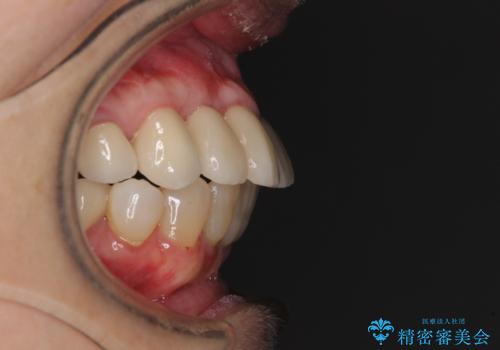

数多くの外科処置を行ったため、治療期間は長期間となりました。

一方、外科処置をしっかりと行ったことで、歯周病の状態は改善され、安定した状態にしあげることができました。